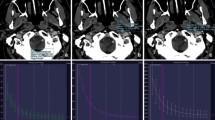

In a diagram of the X-Map algorithm (Fig. 9), it is assumed that the brain parenchyma mainly consists of three materials: gray matter, white matter and water. The X-Map emphasizes water content as a hypo-dense lesion in the brain parenchyma by suppressing a difference in the lipid content between the white matter and the gray matter. It projects all voxels plotted in the diagram along the lipid-specific slope of 2.0 at 80 kV and Sn150 kV settings onto the baseline that is connected between the nominal point of water and the nominal point of gray matter (33 HU at Sn150 kV and 42 HU at 80 kV). This mathematical operation can generate the virtual gray matter map and all relevant voxels in the brain parenchyma are placed on the baseline. Therefore, the voxels with increasing edema containing a large fraction of water content will be located rather far from the nominal point of gray matter and closer to the nominal point of water on the baseline [26].

The X-Map uses a modified 3MD algorithm. A motivation of this application is to visualize an ischemic change of the brain parenchyma by detecting an increase in water content in a voxel. To identify a small change in water content, the 3MD algorithm had a lipid-specific slope of 2.0 applied in order to suppress the small difference between gray matter and white matter, which is mainly the difference in the lipid content in gray and white matter. As shown in the diagram, the nominal values of gray matter and white matter are 33 HU at Sn150 kV and 42 HU at 80 kV, and 29 HU at Sn150 kV and 34 HU at 80 kV, respectively. The lipid-specific slope between the nominal point of gray matter and white matter is 2.0 using the third generation DSCT (SOMATOM Force; Siemens Healthcare, Forchheim, Germany)